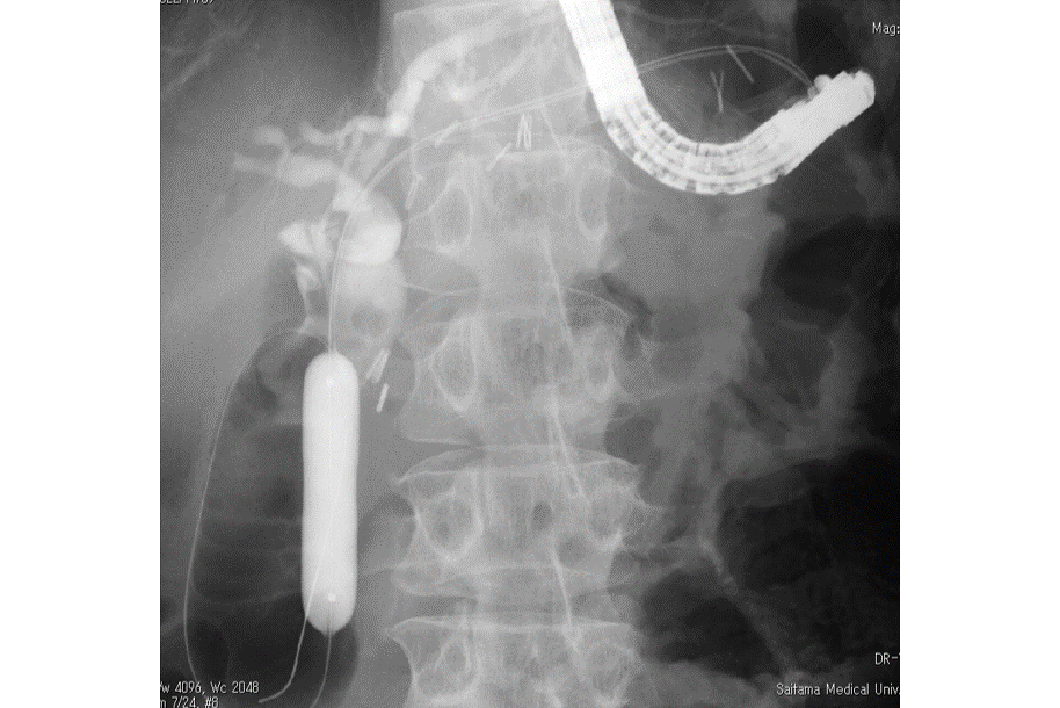

胆石(胆管結石)に対する内視鏡治療(ERCP)を多数行っており、巨大な結石や胃の手術後などの治療困難症例でも対応が可能です。

慢性膵炎に合併する膵石は、痛みや急性増悪の原因となります。膵石は固く、慢性膵炎による膵管狭窄をしばしば伴うため内視鏡的治療が難しい場合も多いです。当院は膵石治療が可能な体外衝撃波破砕(ESWL)装置を保有しており、治療経験が豊富な専門医が治療戦略を立て、治療にあたります。

治療困難な胃静脈瘤に対してはシアノアクリレートを用いた硬化療法とバルーン下逆行性経静脈的塞栓術(BRTO)を実施し、緊急止血と予防的治療に良好な成績を上げています。